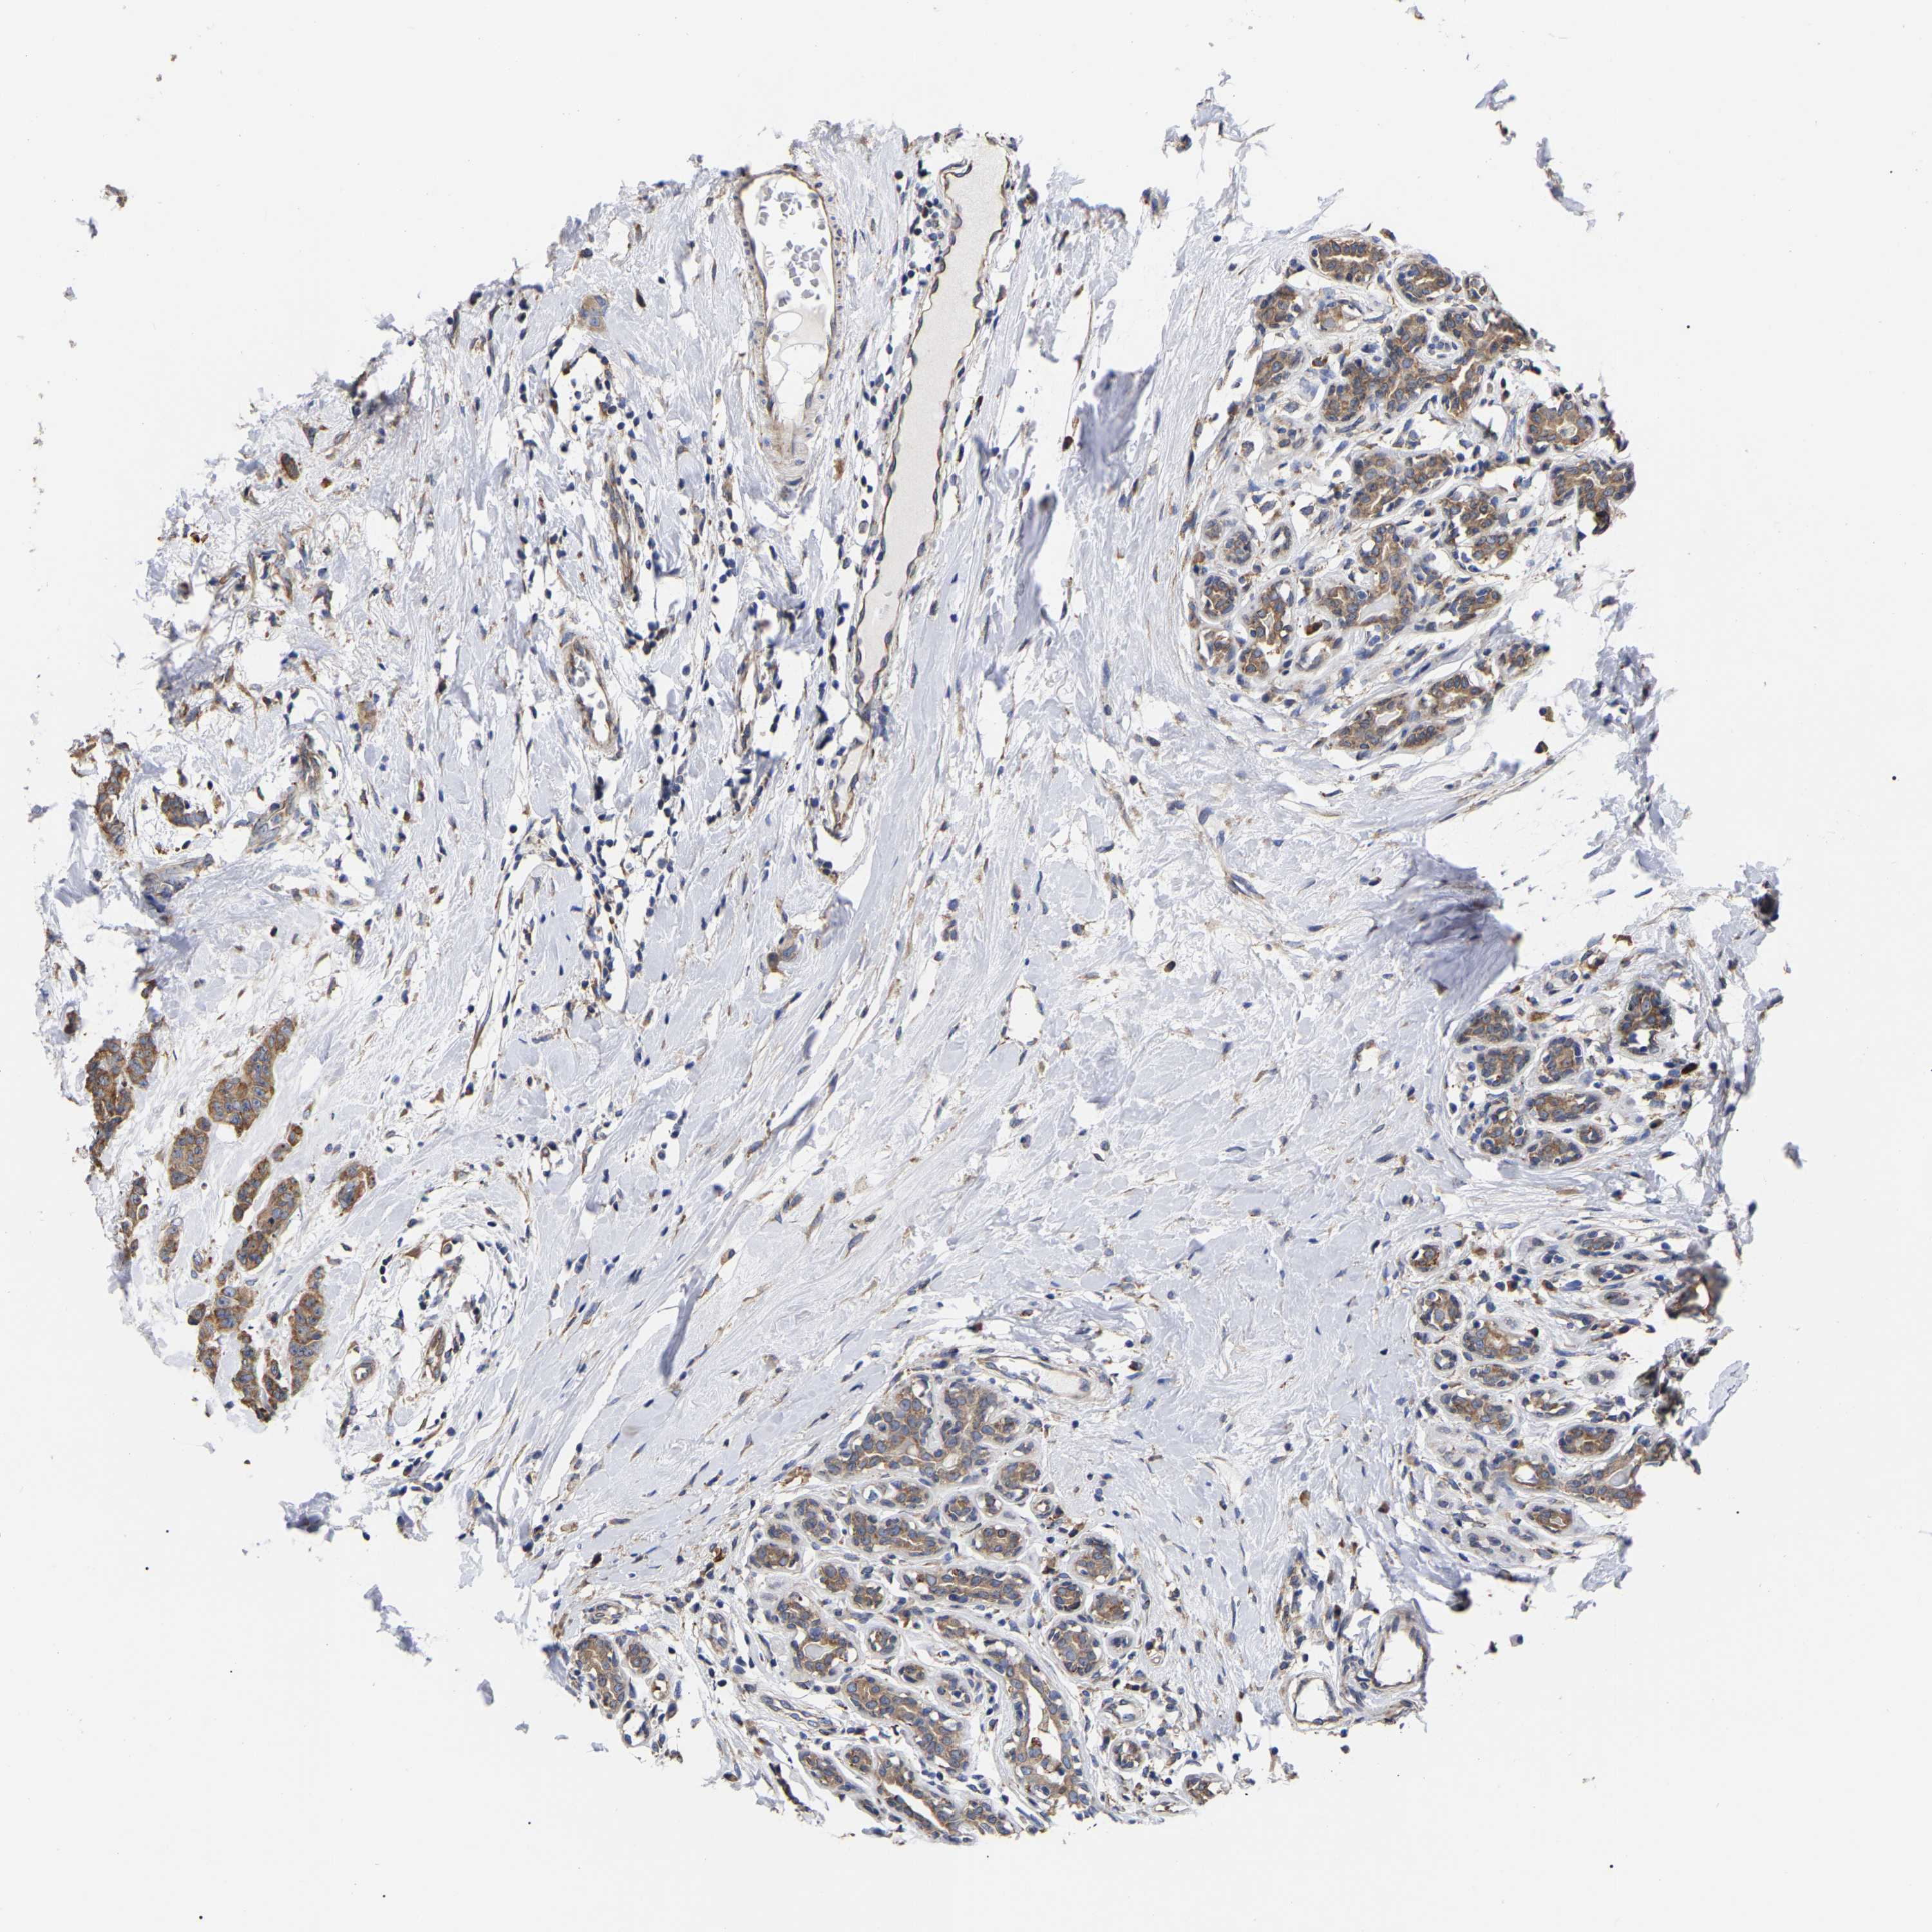

CANCER BREAST CANCER Show tissue menu

BRCA TCGA BRCA VALIDATION PROTEIN EXPRESSION